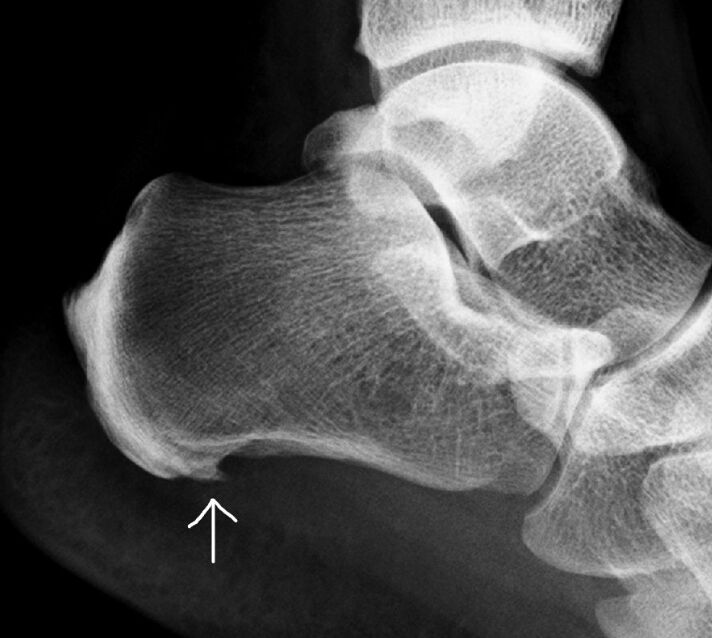

2. X نۇردا تەكشۈرۈش:بۇ سۆڭەك ئۆسۈپ قېلىشنى باھالاشتىكى ئەڭ كۆپ قوللىنىلىدىغان ئۇسۇل بولۇپ، سۆڭەكنىڭ شەكلى ۋە ئورنىنى ئېنىق كۆرسىتىپ بېرەلەيدۇ.